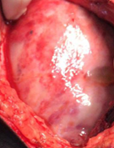

The two metastatic foci causing stenosis and bowel obstruction are clearly visible (Courtesy Dr. V. Penopoulos)

After opening the specimen, the metastatic foci are clearly visible (Courtesy Dr. V. Penopoulos)